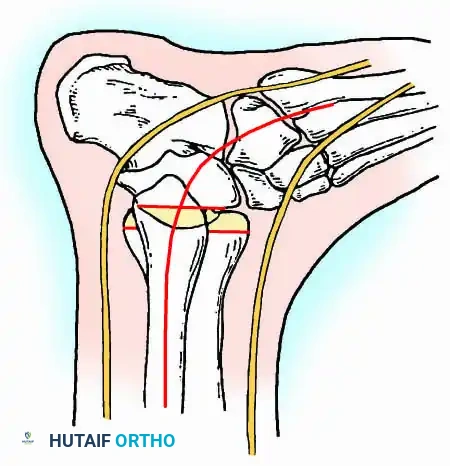

Transmalleolar (Transfibular) Approach

This approach utilizes a lateral incision over the distal fibula. A transfibular osteotomy is performed, reflecting the distal fibula distally or excising it entirely to be used as autograft. This provides unparalleled exposure of the lateral half of the joint and the posterior facet. It is highly effective for correcting severe varus/valgus deformities. A supplementary medial incision (medial malleolar osteotomy) can be added for complete joint exposure.

A standard construct involves two or three screws:

1. A "home run" screw directed from the posterior malleolus into the anterior neck of the talus.

2. A screw from the medial malleolus into the lateral body of the talus.

3. A screw from the anterolateral tibia into the medial talar body.